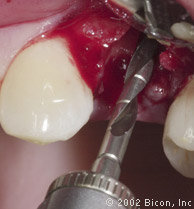

4. | 用2.0mm的先锋钻预备牙槽骨。 |